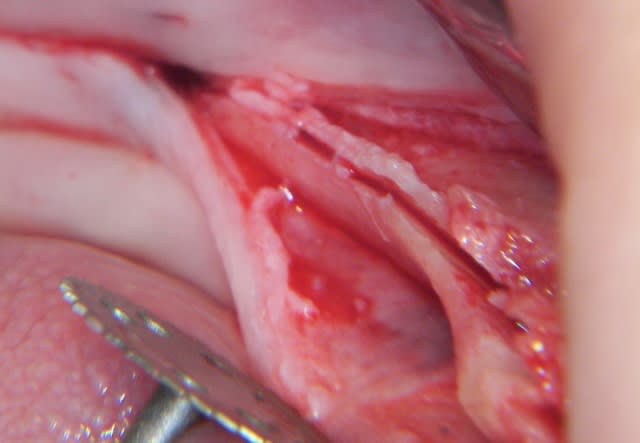

voici peut être une autre solution qui te satisfera d'avantage car beaucoup plus simple à mettre en œuvre.

c'est une simple ROG avec des vis pour maintenir l'espace sous la membrane.